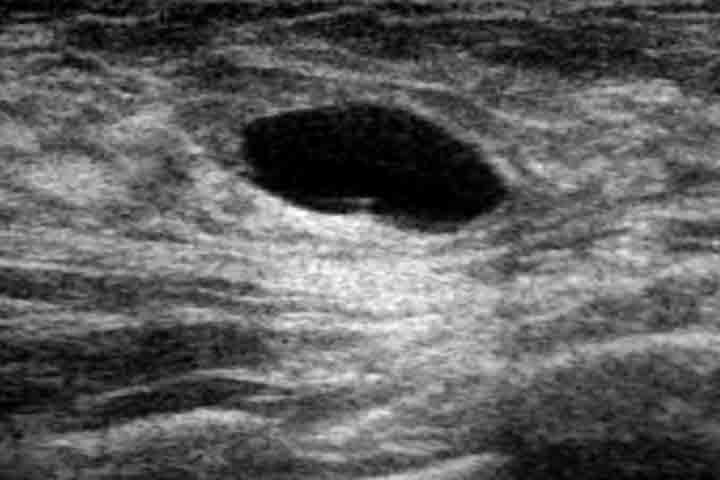

تجريف الإبط هو إزالة النسيج الدهني والعقد اللمفاوية الموجودة في ناحية الإبط (تحت الذراع في مكان اتصالها مع الصدر). ويتم ذلك في نفس العملية، حيث يجرى من خلال نفس الشق الجراحي في حالات استئصال الثدي الكامل، أو من خلال شق آخر صغير تحت الإبط في حالات استئصال الكتلة السرطانية فقط.

وهذا الإجراء هو جزء أساسي من عمليات سرطان الثدي، وذلك لتنظيف العقد اللمفاوية التي قد تكون مصابة بالورم. كما أنه مهم جداً في تصنيف مرحلة الورم من خلال تحليل العقد المستأصلة بعد العملية، وبالتالي تحديد العلاج التكميلي الضروري الذي ستحتاج إليه المريضة.

يشير تورم اليد أو الذراع بعد عملية سرطان الثدي مع تجريف الإبط إلى حالة الوذمة اللمفاوية. تحدث هذه المشكلة بسبب تجمع السوائل في الذراع بسبب انقطاع الأوعية اللمفاوية المسؤولة عن سحب السوائل منها. وهي من المضاعفات الشائعة بعد عمليات الإبط. إذا كان لديك انتفاخ في اليد أو الذراع فعليك أن تقرئي مقالة الوذمة اللمفاوية في الذراع بعد عمليات الثدي، فهي تحتوي على معلومات هامة جداً حول التعامل مع هذه المشكلة.

في بعض الأحيان تجف السوائل التي تخرج عبر الأنبوب فيقوم الطبيب بسحب الأنبوب بشكل طبيعي. وقد يحدث وأن تستمر الإفرازات الداخلية بشكل خفيف بعد ذلك مما يؤدي إلى تجمع الماء بداخل الجرح وحدوث تورم في الجرح. تدعى هذه الحالة بالورم المصلي بعد تجريف الإبط، وهي من المشاكل الشائعة بعد العملية. ويمكن للطبيب تشخيص هذه الحالة ببساطة بمجرد إجراء الفحص.

يحتاج العلاج في هذه الحالة إلى سحب السوائل من الجرح بواسطة الإبرة. يتم إدخال إبرة عادية عبر الجلد وسحب السوائل الموجودة في الداخل إلى أن يتم إفراغها بشكل كامل. قد تتجمع السوائل مرة أخرى بعد السحب، ولذلك يتوجب على المريضة أن تعود مرة أخرى لإجراء الفحص خلال أسبوع على الأكثر. وفي حال تجمع السوائل مجدداً فإن ذلك يحتاج إلى إعادة السحب مرة أخرى.